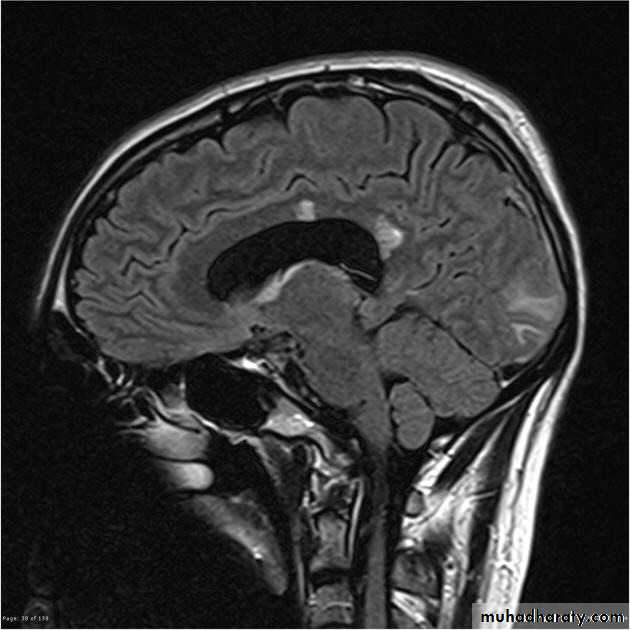

MRI :characteristic abnormalities are found in >95% of patients, although more than 90% of the lesions visualized by MRI are asymptomaticLesions are frequently oriented perpendicular to the ventricular surface,(Dawson’s fingers)

Lesions larger than 6 mm located in the corpus callosum, periventricular white matter, brainstem, cerebellum, or spinal cord are particularly helpful diagnostically